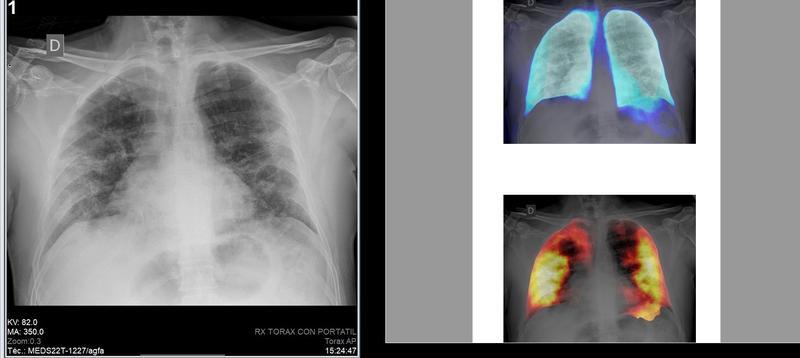

En 2020 se realizaron en España alrededor de 43 millones de pruebas de diagnóstico por imagen, con un valor global de 2.700 millones de euros, según el Observatorio Sectorial DBK de Informa, filial de Cesce.

El observatorio estima que el número de pruebas fue un 15,5% inferior al contabilizado en 2019, debido al impacto de la pandemia de la Covid-19 en la actividad de los centros de diagnóstico por imagen, que supuso la paralización de gran parte de las pruebas en la primera mitad del año y la posterior limitación de afluencia debido a los protocolos de seguridad.